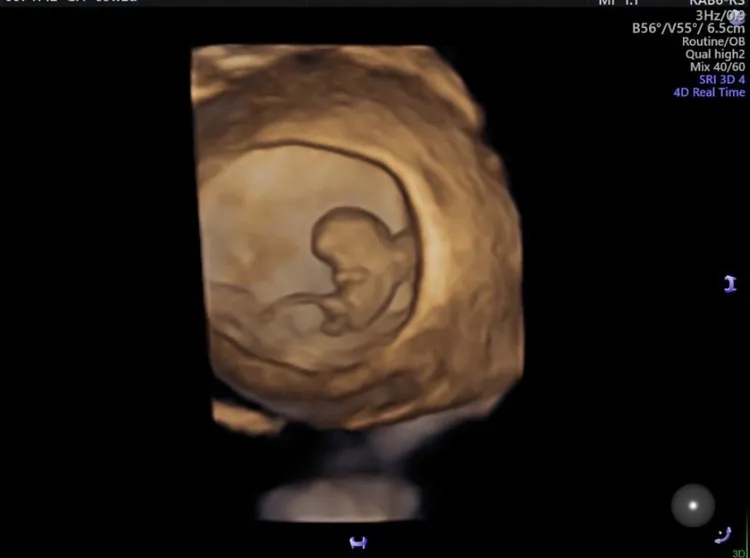

蘇怡寧在粉絲頁上分享胎兒超音波照,只見照片中的胎兒身上掛著長長的一根,蘇怡寧寫道:「各位同學,請不要隨便看到一根東西就說是GG,不管你想不想要,就不是,『這根是臍帶』,謝謝。」

其他網友看了以後也紛紛笑說「我不爭氣的大笑了!哈哈哈哈哈」、「哈~爺爺爸爸一定很驕傲」、「如果是GG,這孩子未免太傑出了吧」、「是唧唧他可以參加世界紀錄了」、「誤會真大」、「這麼小也看不到GG」、「笑到往生」'「GG真的沒有那麼長⋯有點常識跟知識啦!不要只會嘗試跟姿勢!」

還有網友納悶地說「這如果是GG也太天賦異稟了吧」、「這GG的比例!!!!應該世界紀錄了吧」、「小小年紀就30cm」「這些家長要是胎兒GG這麼長,不擔心有異常嗎?」「小時了了?!」「爸媽希望自己的兒子是世界長的尺寸」、「撐竿跳了」、「嬰兒屆冠軍的GG」。